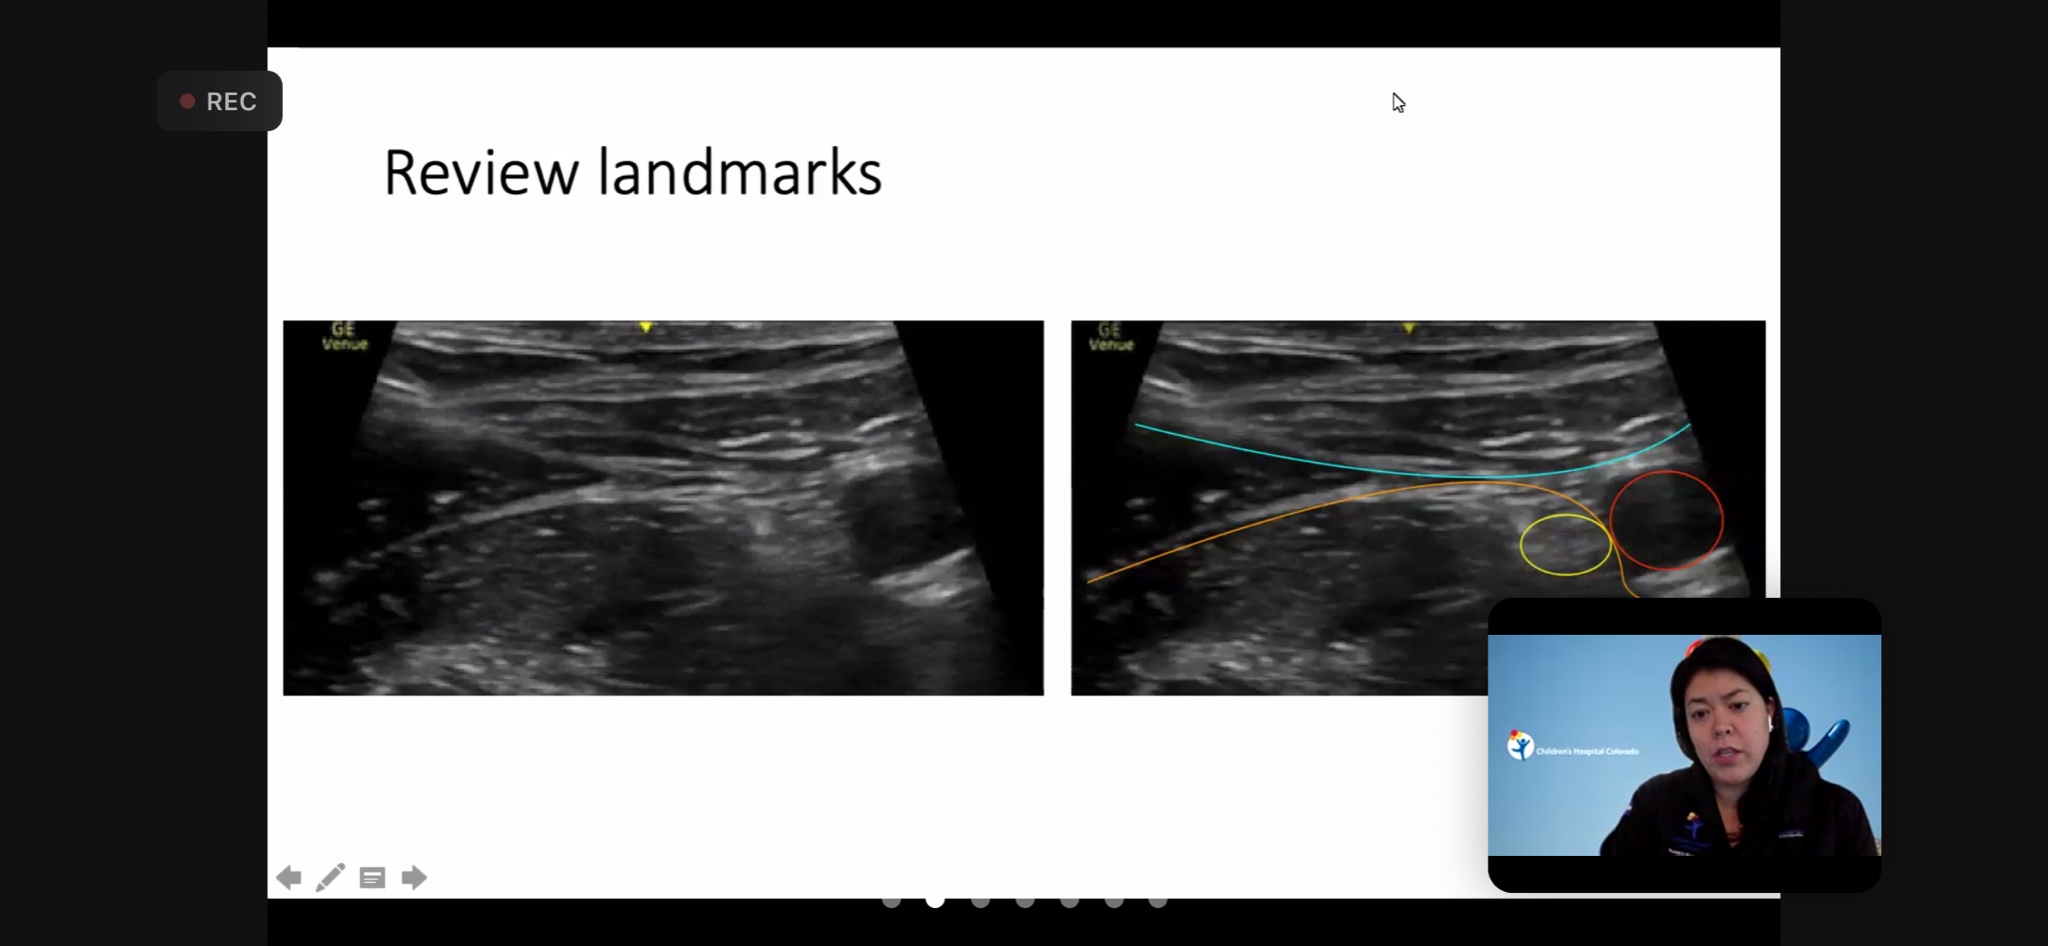

Pediatric emergency physician Julia Brant presented at the national P2 Network (PEM POCUS) conference on 5/25/21 about a multi-center collaboration on ultrasound guided fascia-iliaca blocks in the pediatric emergency department. Her presentation, "Case Series: Pediatric Ultrasound-Guided Fascia Iliaca Compartment Nerve Block", represented a collaboration with the University of Louisville Department of Pediatrics, Children's Hospital Colorado, the Hospital for Sick Children (Toronto), Yale University, University of Massachusetts, and Denver Health Emergency Medicine.